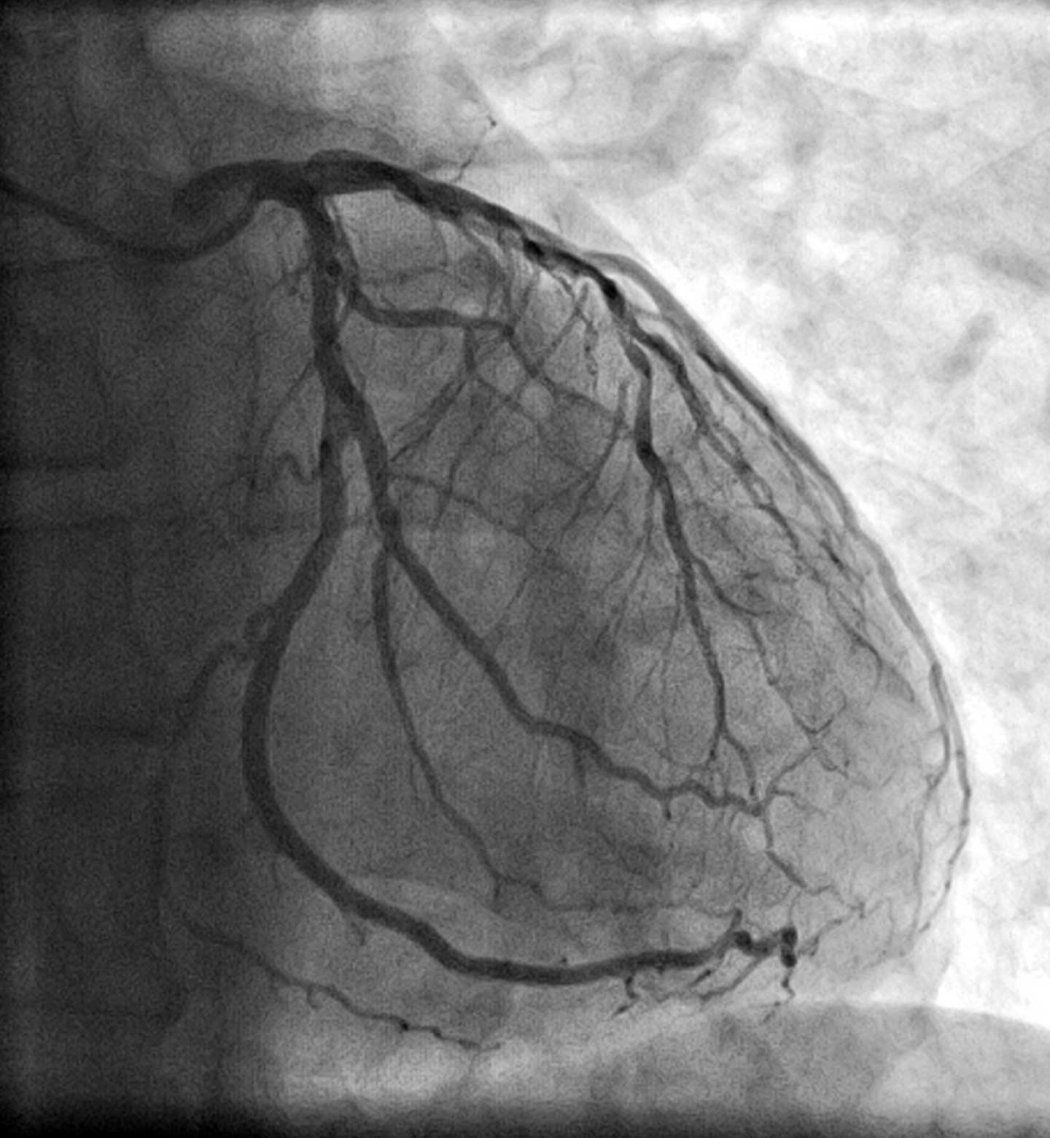

Well, Yes and No. Our recent research, published in JAMA Cardiology used deep neural networks, a type of AI algorithm called CathEF, to predict how much blood a heart was pumping using standard angiogram videos – x-ray images that visualize the inside of blood vessels, in particular arteries, veins and the heart chambers – with the goal of gaining new insights into possible patient treatment in critical situations.

We fed it coronary angiograms of more than 4,000 of patients along with corresponding transthoracic echocardiograms – or coronary ultrasound tests of 3,600 patients. Angiograms and echocardiograms are the standard diagnostic assessment for nearly all heart disease related decision-making, from medications to coronary bypass surgery, so just about everyone with heart and stoke issues has them done.